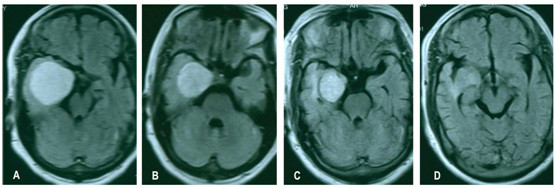

射波刀治疗脑膜瘤成功的案例

射波刀治疗脑膜瘤案例

射波刀治疗颅内肿瘤越小效果就越好!